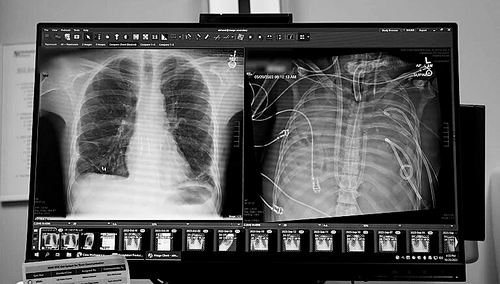

X光片显示的一名33岁患者的新肺(左)和旧肺。图片来源:美国西北大学